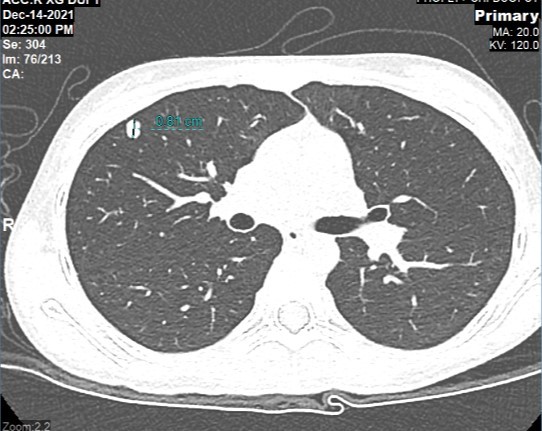

Hình chụp CT phối của cháu Khánh Thơ phát hiện khối u di căn phổi sau 1 năm phẫu thuật cắt bỏ u khớp gối. |